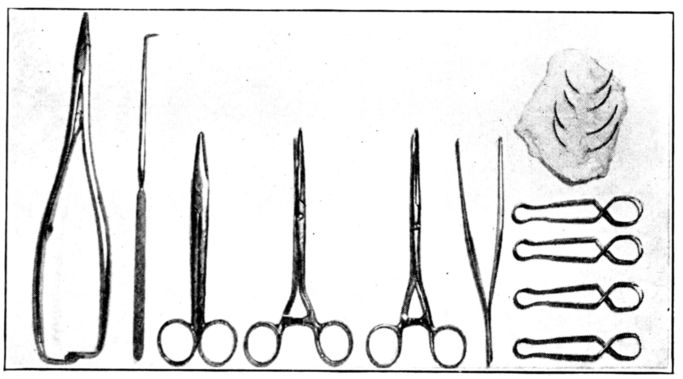

| 80. | Instruments shown in Fig. 79 | 260 |

| 81. | Old prints showing early methods of delivery | 261 |